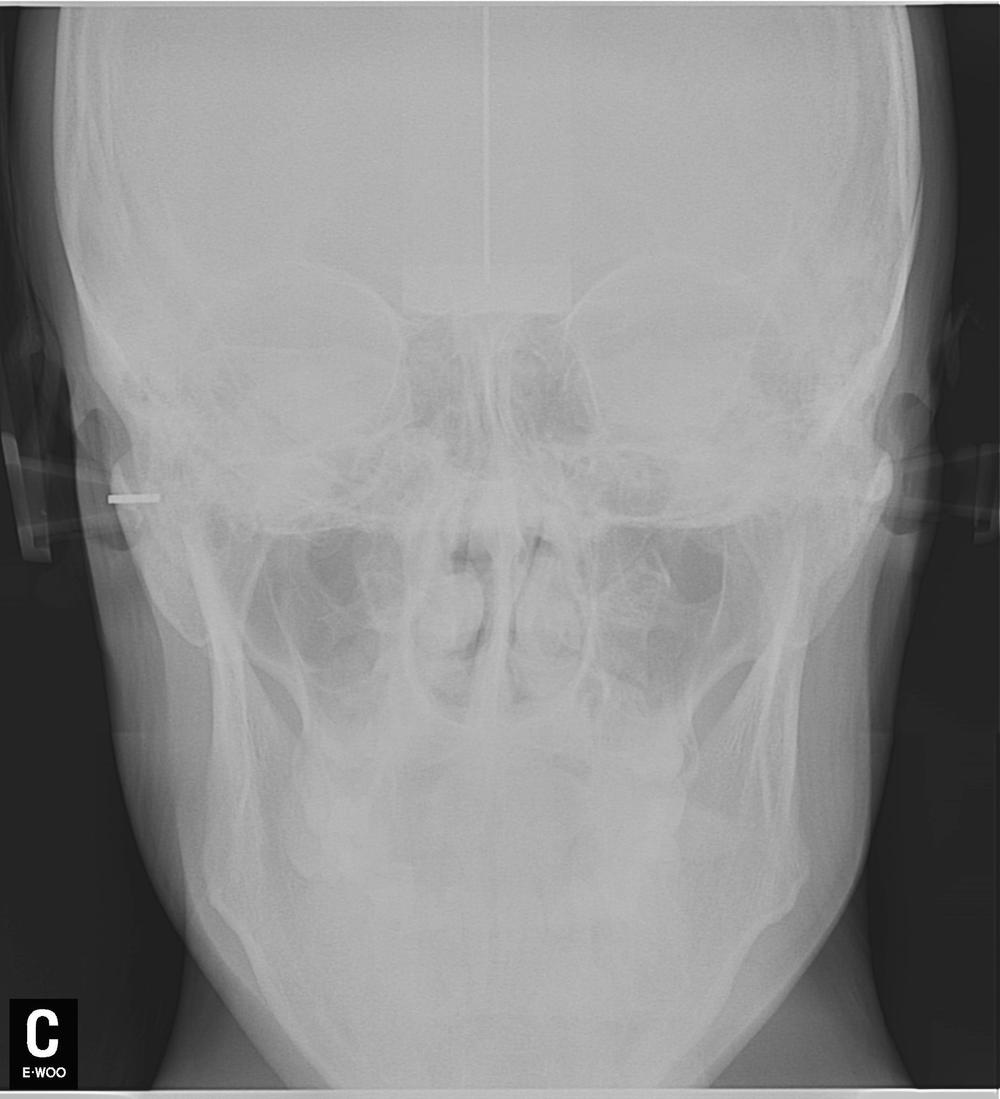

Вам сказали фигню! Вот снимок этой пациентки до лечения.

Как стоматолог, поясняю - здесь проводится ортодонтическое лечение. Явно не просто так, у пациентки были проблемы прикуса, которые привели к снижению межальвеолярной высоты. Это означает, что нижняя челюсть вывернута вверх и кпереди от своего нормального положения, что приводит к перенепряжению групп мышц вплоть до нарушения кровоснабжения головы и шеи. Кто не видит логики - постоянный гипертонус мышц пережимает сосуды. Попробуйте выдвинуть нижнюю челюсть вперед и кверху - через несколько минут заболит голова. При снижении высоты прикуса это становится хроническим, организм начинает рефлекторно сбрасывать это напряжение задействуя другие группы мышц.